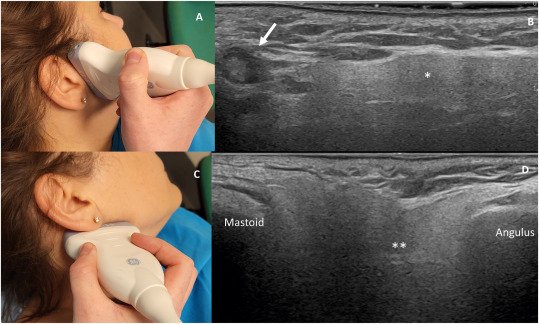

High-resolution digital imaging for detailed cellular analysis.